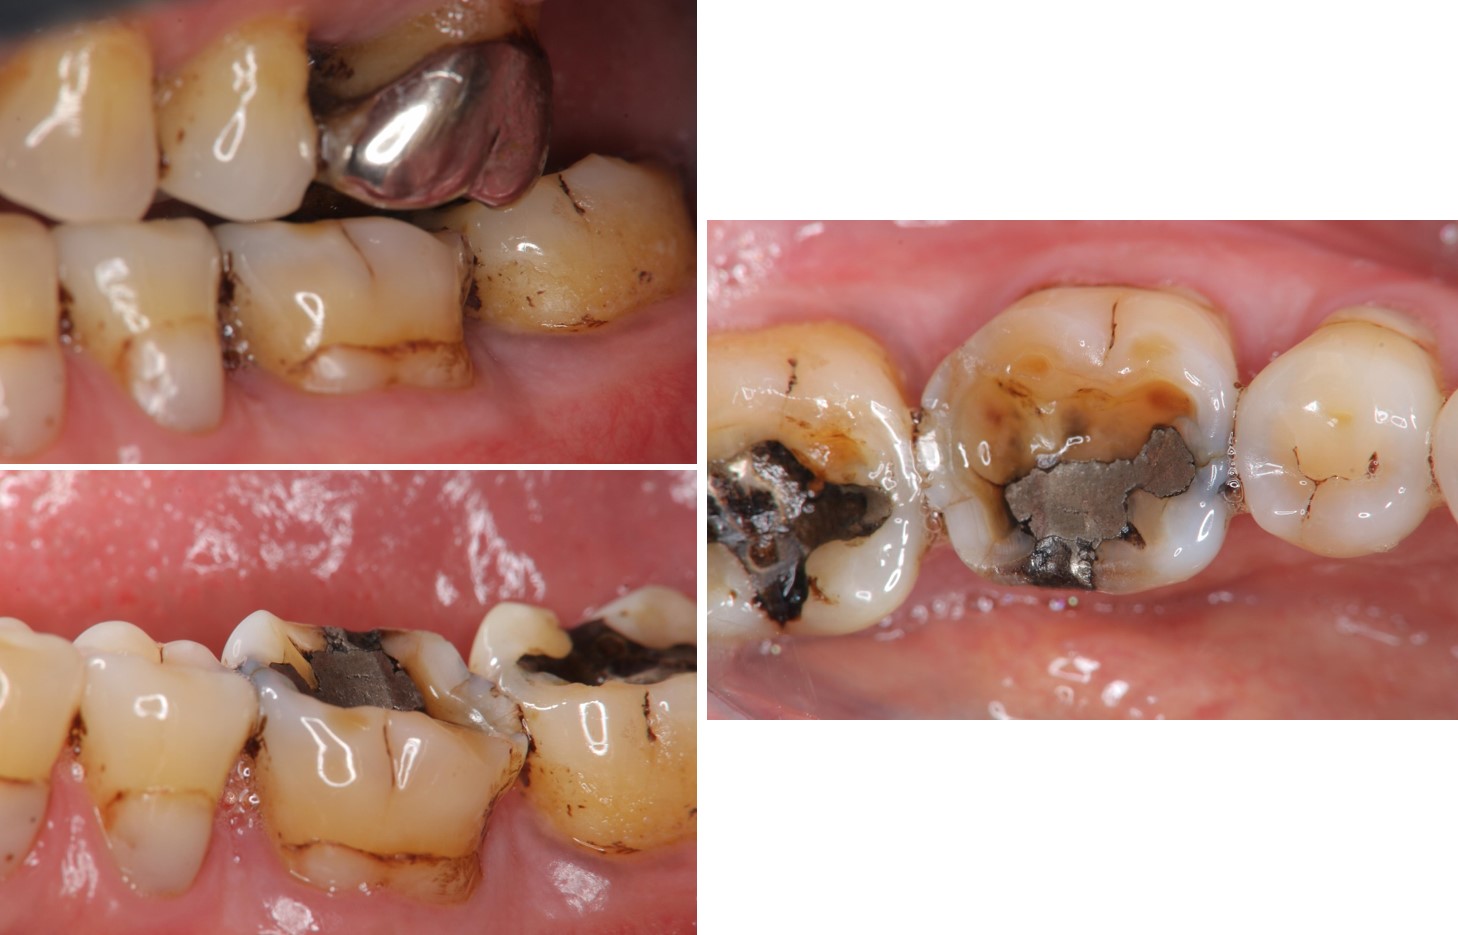

治療前,牙齒嚴重磨耗

治療前,牙髓仍未受侵犯